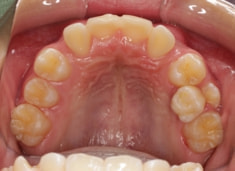

検査時のレントゲン分析では、上下顎の関係は、上顎の劣成長があり下顎前突傾向という値がでておりましたが、前歯ジャンプ後はフェイスマスクの効果もあり、上下顎の関係は正常化しています。

上顎が若干優位になっていますので、今後の下顎の成長のための貯金になっているくらいです。